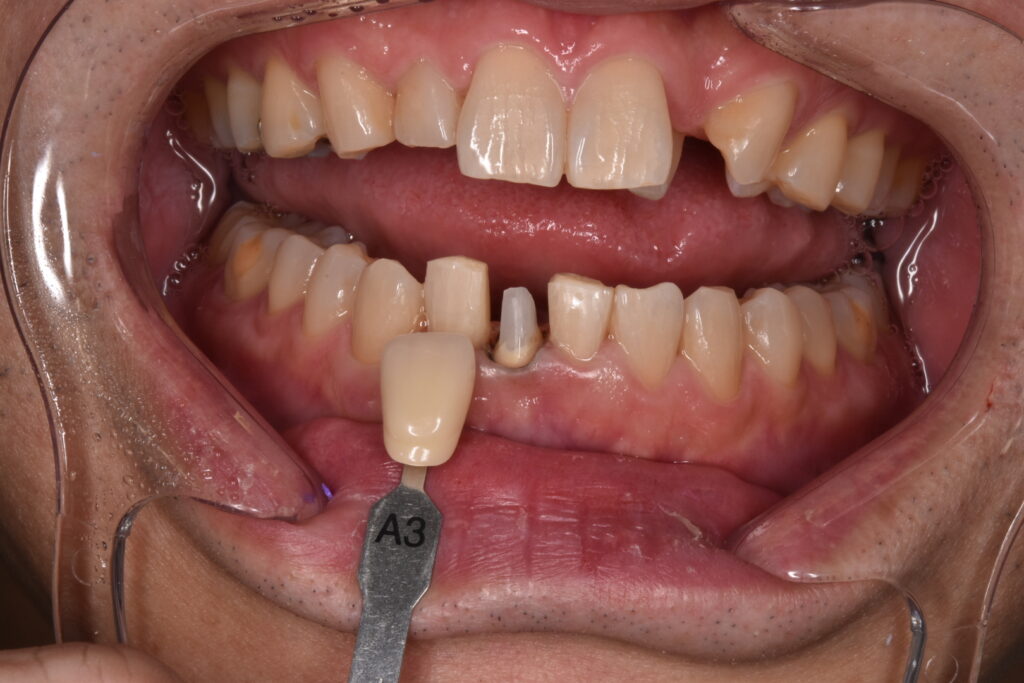

完成したセラミック

さくらジルコニアプランでのジルコニアセラミックです。歯の色はA3というシェードです。色見本が20色近くありますので、そちらから選択して頂きます。